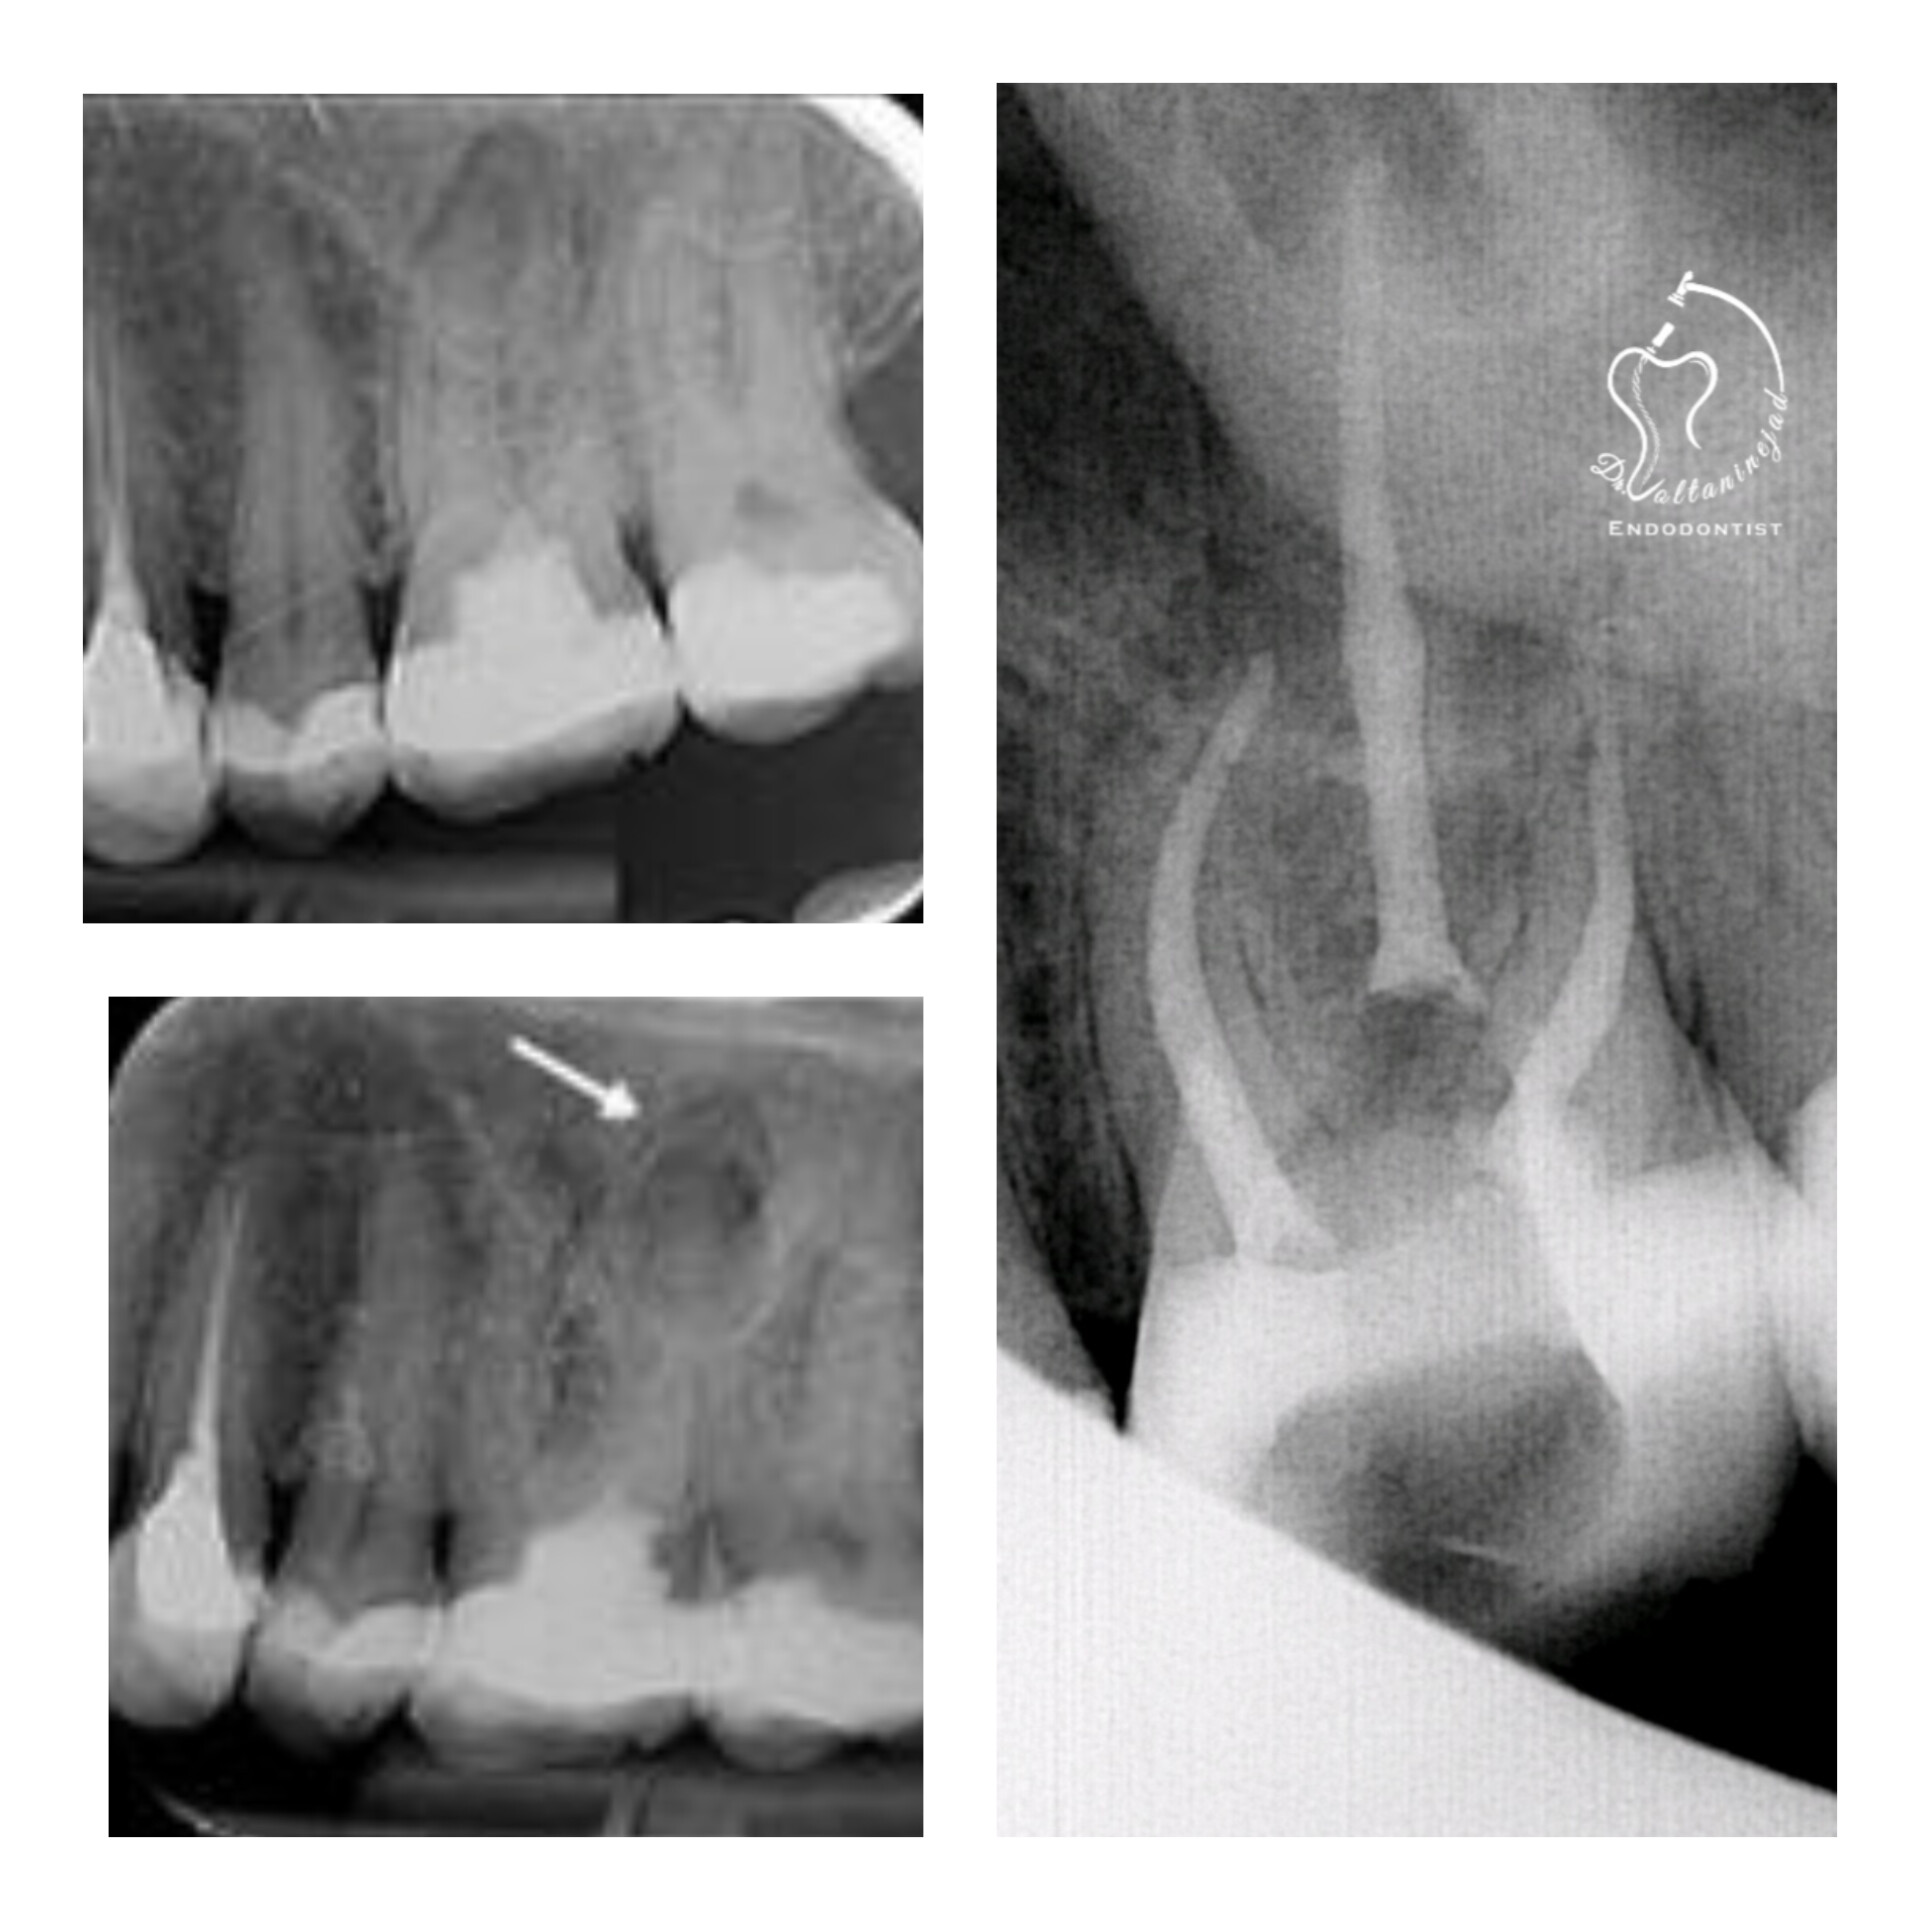

🔹 درمان ریشه دندان کانین با ضایعه وسیع

• شرح کوتاه: بیمار با درد و تورم شدید مراجعه کرد. پس از درمان ریشه تخصصی، ضایعه استخوانی طی ۶ ماه به‌طور کامل بهبود یافت.

• نتیجه: حفظ دندان و بازگشت عملکرد طبیعی.

🔹 خارج کردن فایل شکسته از کانال

• شرح کوتاه: بیمار با درمان ریشه نامناسب و فایل شکسته در کانال مراجعه کرد. فایل با میکروسکوپ خارج شد و درمان ریشه مجدد انجام شد.

• نتیجه: رفع درد و حفظ دندان بدون نیاز به جراحی.